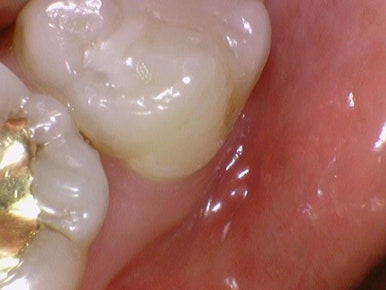

치아색 세라믹인레이 세라믹 중에서도

치아색을 위해서는 이맥스(E.max) 라는 재료를 사용하고 있습니다.

많이 검색해본 분들은 아시겠지만

이맥스 인레이는 인레이 재료로 많은 치과에서 선호하고 많이 사용하는 인레이의 대표 재료입니다.

레진 인레이, 하이브리드인레이, 지르코니아 인레이 등 치과마다 사용하는 하얀색 인레이 종류가 다른데

저희 경험상으로는, 그리고 저희가 여러 논문들과 학술자료들을 검토했을 때

현재로서는 이맥스 인레이가 가장 잘 안깨지고, 접착도 잘 되어서

인레이로서는 가장 이상적이라고 생각해서 사용하고 있습니다.

저희 치과에서는 인레이 재료로는 이맥스(e-max) 인레이를 사용하고 있습니다.

색상도 치아와 비슷하여 금 인레이처럼 티가 나지 않습니다.